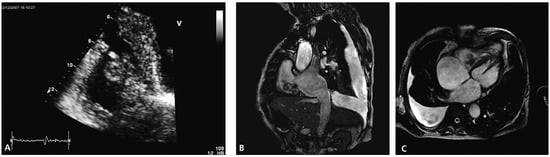

Echocardiography two months later revealed a slightly improved left ventricular ejection fraction (30–35%) and an obvious reduction in size of the thrombus (Figure 2A).

Figure 2.

Echocardiographic follow-up images. Note the increase in size and the prolapsing part of the thrombus in panel (B).

Follow-up echocardiography was performed again half a year later. At that time, the size of the right ventricle appeared normal whereas the systolic right ventricular function was still reduced (TAPSE 1.8 cm, TDI 9 cm/s). The thrombus had increased in size with new highly mobile parts prolapsing into the right atrium (Figure 2B). The patient passed away at home seven months later from an unknown reason.